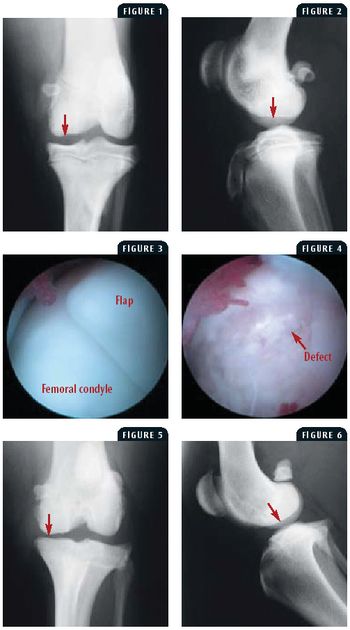

A 7-month-old intact male Labrador retriever was presented for evaluation of a two-week history of left hindlimb lameness.

Minimally invasive surgery is a rapidly developing discipline in veterinary medicine, thanks to its widespread use in human medicine. During the past 20 years, veterinarians have watched a temporally similar development with arthroscopic surgery.